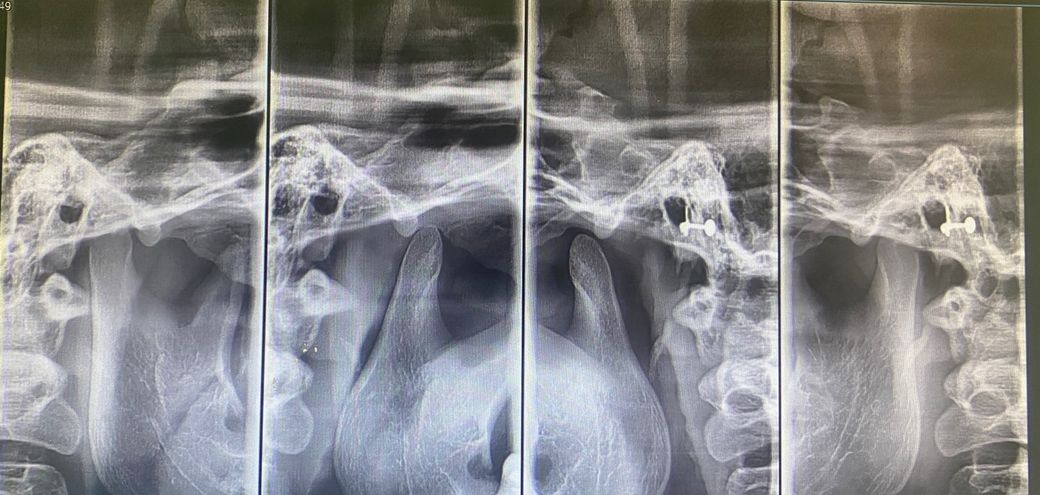

턱관절이 뒤로 밀린건지, 관절 내 공간이 좁은지, 뼈가 갈렸는지, 턱관절 모양 자체가 불리하다던지 등등.. 문제가 있을까요

사진은 같은 날 찍은게 아니고 2달정도의 날짜 간격이 있습니다. 둘다 턱관절 증상 있을 때입니다

제가 보기엔 오른쪽 관절 내 공간이 더 좁고, 하악도 오른쪽이 더 뒤로 들어가있는건 맞는 것 같거든요..

근데

왼쪽도 위치 상의 문제가 있는지도 궁금하고

과두 모양도 오른쪽이 더 얇아진 것 같은데 ..

• 1번 째 사진

• 2번 째 사진